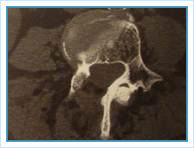

Técnica quirúrgica descrita en el año 1988 por Yeung. Se realiza un abordaje por la parte posterior de la columna con un sistema tubular (METRx) con una incisión de aproximadamente 2,5 cm.

Es un procedimiento que permite realizar descompresiones de la columna lumbar con mínima invasión, ideal en pacientes con estenorraquis lumbar y de edad avanzada. Presenta un porcentaje de complicaciones muy bajo en especial si lo comparamos con la cirugía de columna abierta tradicional.

Debido a la poca agresión de este procedimiento se logran resultados equivalentes a la cirugía abierta pero con un porcentaje de complicaciones menores, menos sangrado, menor porcentaje de inestabilidad de la columna secundario al procedimiento quirúrgico lo que permite un alta precoz del paciente, aproximadamente a los 2-3 días de la cirugía y sin necesidad de permanecer en reposo en cama.